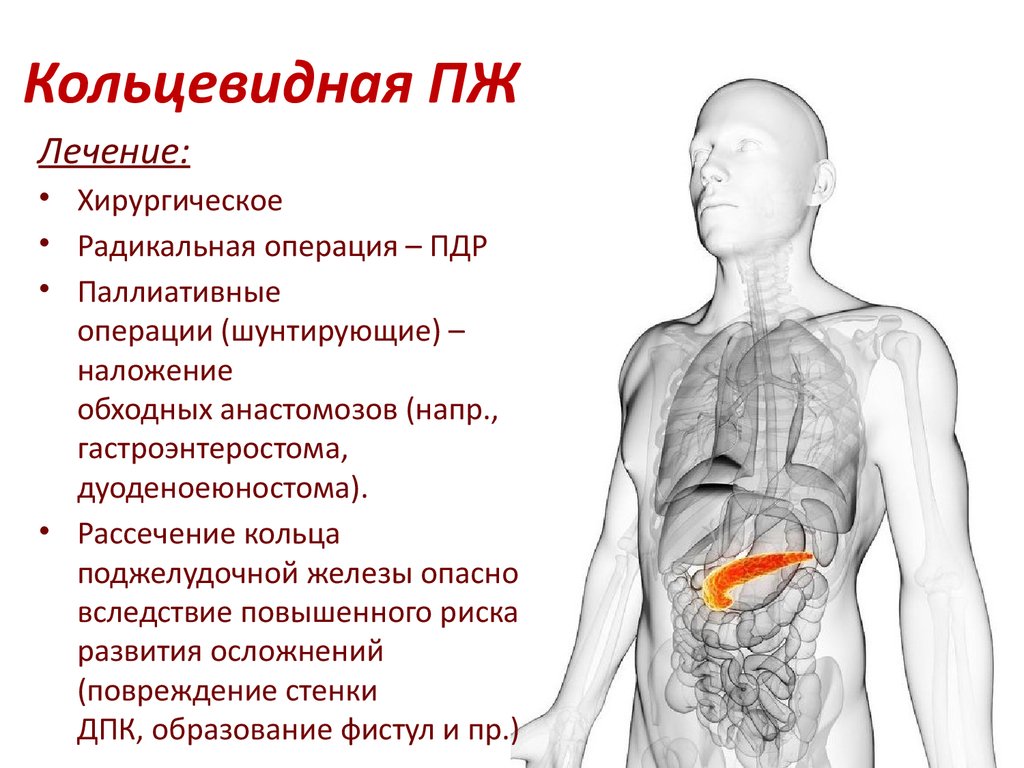

УЗИ диагностика кольцевидной поджелудочной железы: что важно знать

Раздел: Кадры перемен